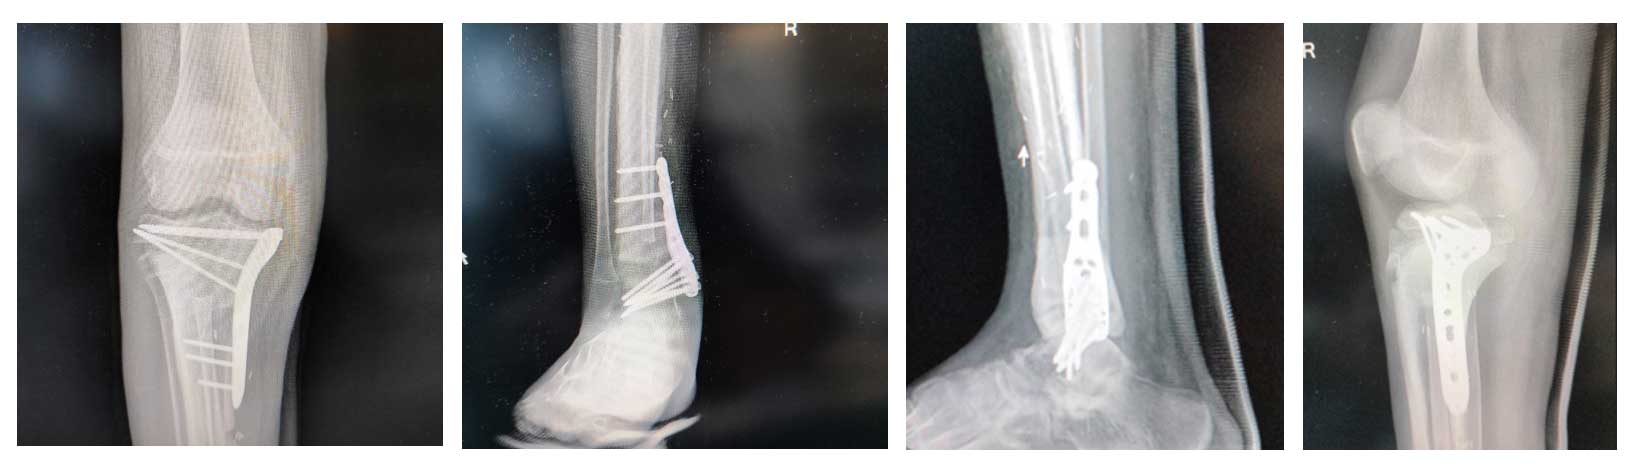

Ameliyat Sonrası: Röntgende anatomik plak ile proksimal osteotomi hattının fiksasyonu ve ayak bileğine artrodez işlemi görülmekte.